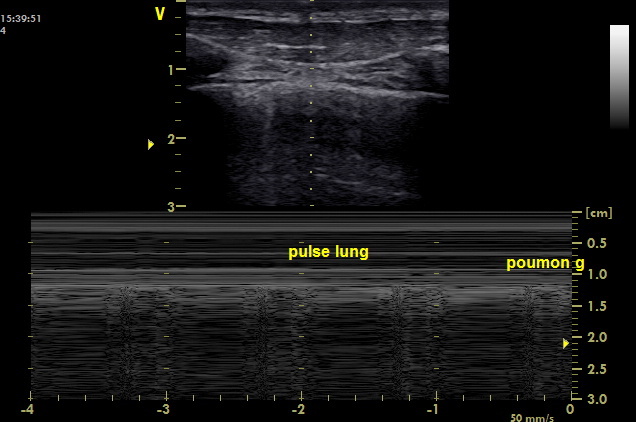

What is the “lung pulse”?

In the non-ventilated lung (ie. mainstem intubation, apnea, complete atelectasis), the visceral pleura will still present with a tiny rhythmic movement synchronous with the cardiac cycle caused by the arterial pulse and movement of the heart itself

***When scanning the left lung, do NOT confuse cardiac movement for lung sliding (ie. lung movement secondary to cardiac movement is known as the lung pulse)